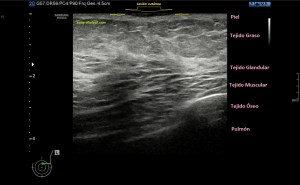

En la imagen 1 observamos la rotura en eje corto, mas flechas rojas señalan el músculo dañado, las amarillas la rotura en si. Observamos la anatomía que la rodea y que es referencia siempre.

Eje largo, con la anatomía de referencia. Observamos las fibras alargadas, rodeadas por el líquido y el abombamiento producido por el sangrado.